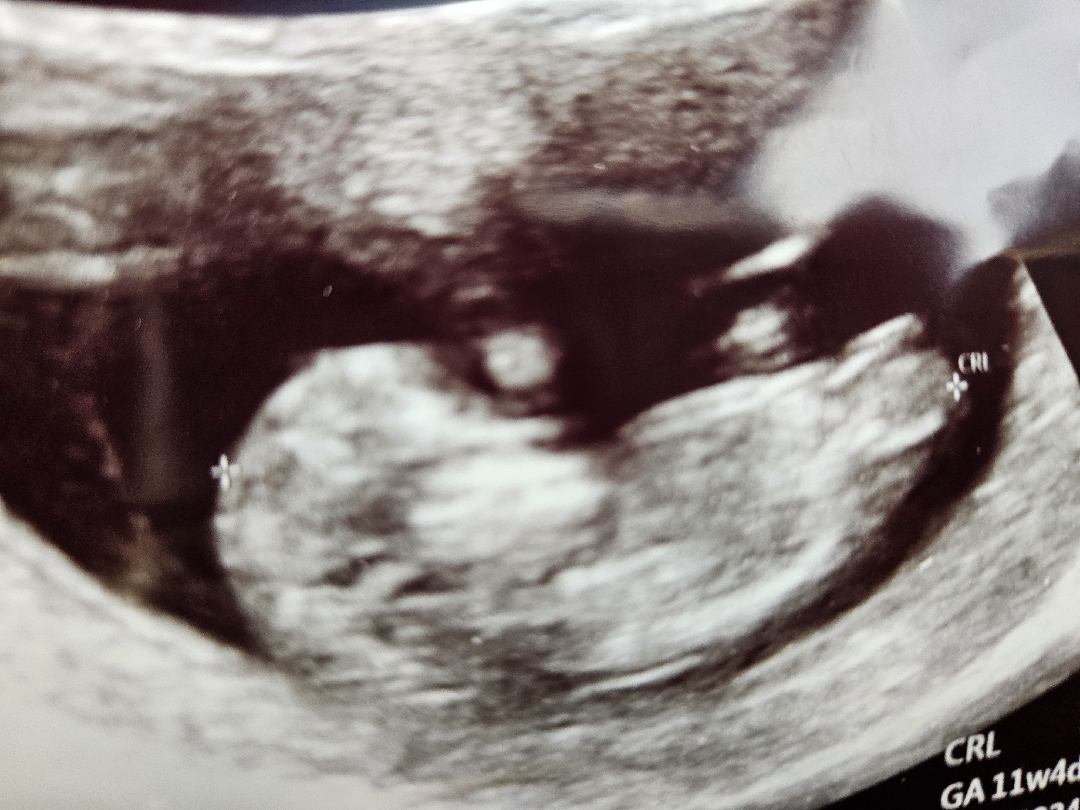

각도법 봐주실 수 있나요?..부탁드려용 ㅠㅠ

각도법 봐주실 수 있을까요? 부탁드릴게용!

딸인거같아영 ㅎㅎㅎ

딸인거같아요~